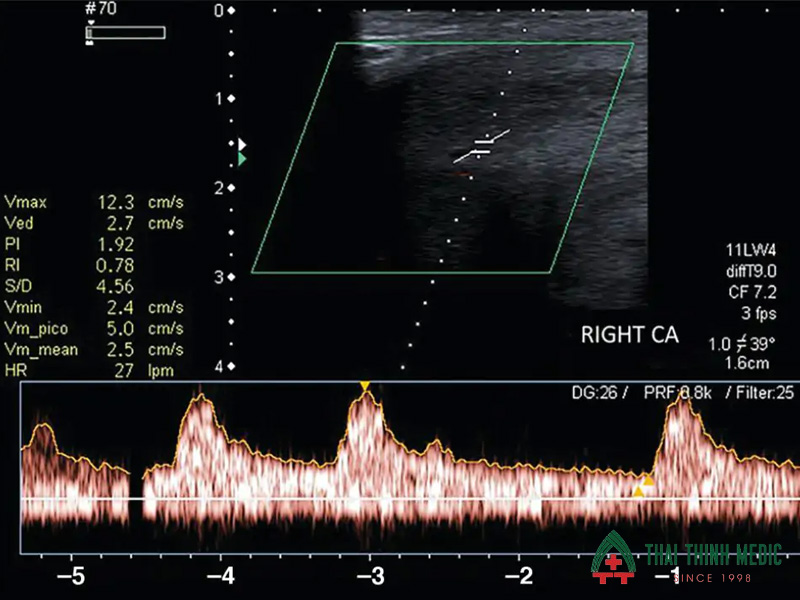

Trong những trường hợp rối loạn cương dương phức tạp hoặc không đáp ứng với điều trị thông thường, các kỹ thuật chẩn đoán hình ảnh và nghiệm pháp chuyên sâu sẽ được áp dụng. Những phương pháp này cho phép bác sĩ quan sát thấy trực tiếp dòng chảy của máu bên trong các mạch máu nhỏ của dương vật và đánh giá phản ứng sinh học của cơ quan này dưới các tác động kích thích thông qua siêu âm Doppler, từ đó đưa ra phác đồ can thiệp chính xác

- Siêu âm Doppler màu mạch máu dương vật để đánh giá lưu động mạch, giúp phát hiện tình trạng rò rỉ tĩnh mạch hoặc hẹp động mạch dương vật.

Siêu âm Doppler dương vật